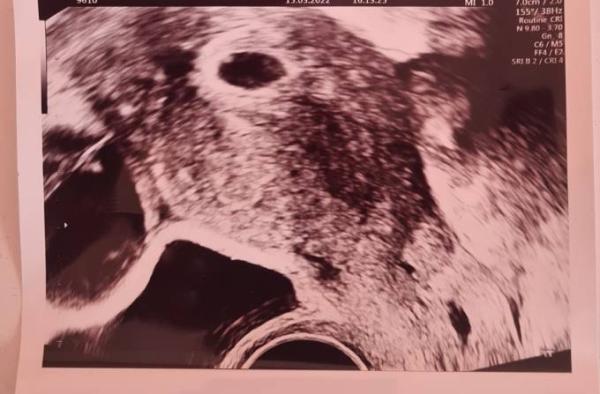

Liebe Community, hatte 4-5 Tage lang eine leichte bräunliche Schmierblutung. Bin dann sofort zum Arzt gefahren und hatte das Ergebnis im Ultraschall. Die Schmierblutung hatte ich danach nicht mehr. Man sieht oben links einen weißen Punkt, muss in der 6ssw noch der Dottersack zusehen sein? Ist das der weiße Punkt oben links?

Der Dottersack ist doch zu sehen. Oben rechts.